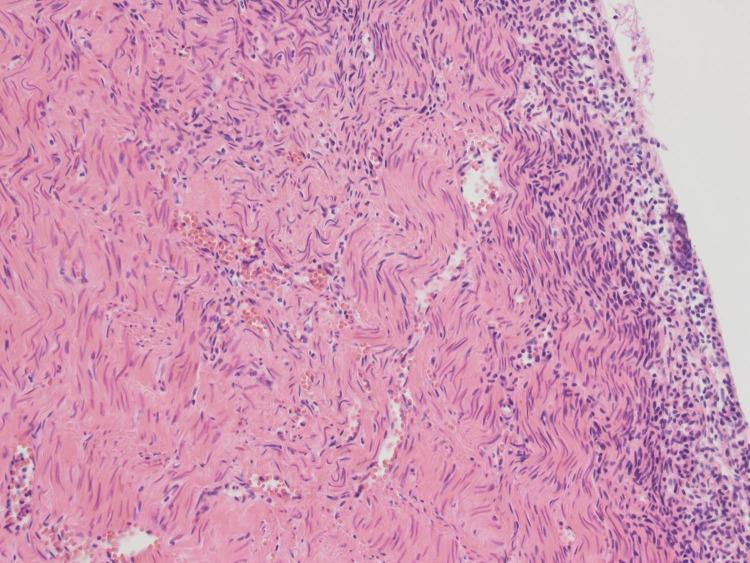

Accessory cavitated uterine mass (ACUM) is a rare and unique condition seen in young women. We report cases of ACUMs in two patients, a 14-year-old girl and a 25-year-old woman, both with complaints of severe dysmenorrhea that had started at menarche and had progressively worsened since. A large cystic lesion was localized in the anterolateral wall of the myometrium separate from the endometrium, which was difficult to distinguish from congenital uterine anomalies. Laparoscopic excision of the ACUMs was successful and completely resolved the dysmenorrhea. Early investigation of severe dysmenorrhea in young women can provide appropriate management and relieve symptoms.

附件性子宫空洞性肿物(ACUM)是年轻女性中一种罕见且独特的病症。我们报告了两例ACUM病例,一名14岁女孩和一名25岁女性,她们均主诉自初潮起就开始出现严重痛经且此后逐渐加重。一个大的囊性病变位于肌层前外侧壁,与子宫内膜分离,难以与先天性子宫异常相区分。腹腔镜下切除ACUM成功,且完全缓解了痛经。对年轻女性的严重痛经进行早期检查可提供恰当的治疗并缓解症状。